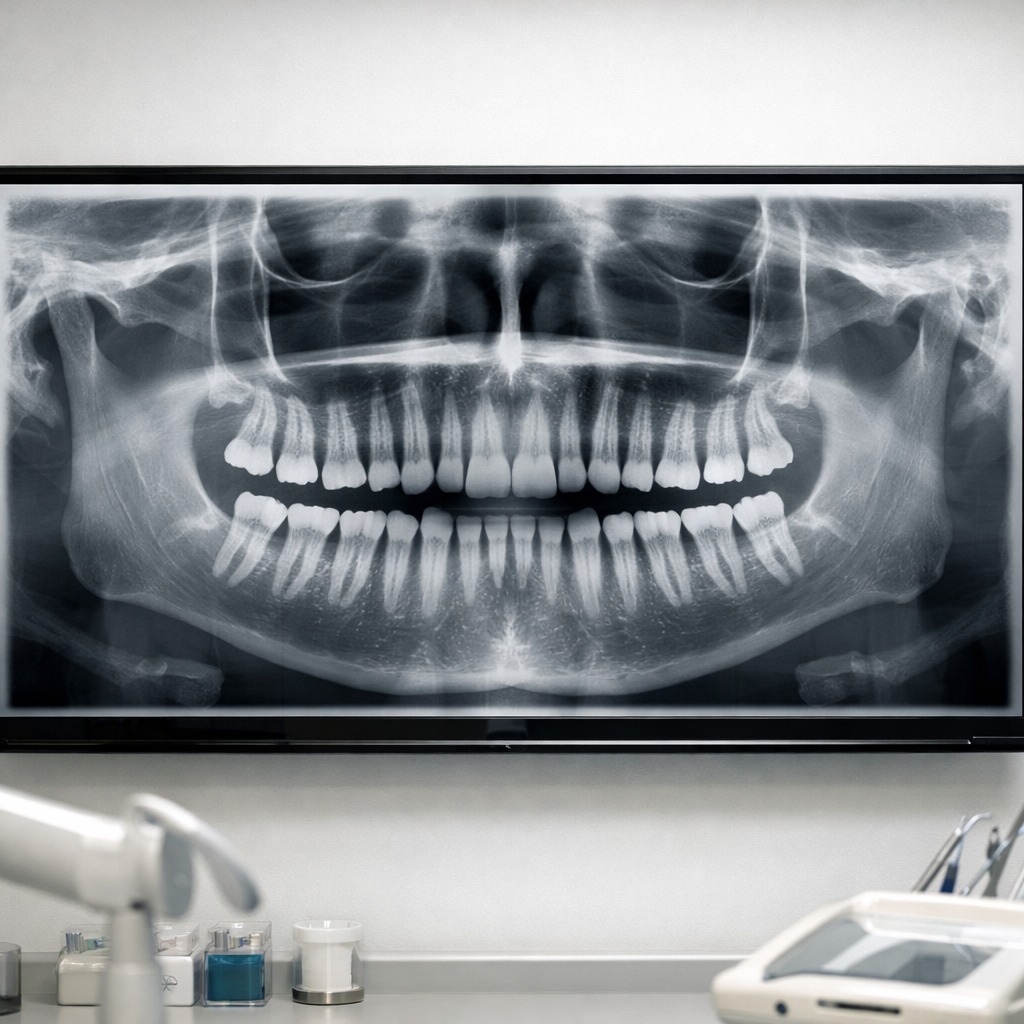

Panoramic X-Rays

Panoramic X-rays capture a complete view of the teeth, jaws, and surrounding structures in a single image. This technology is especially useful for evaluating wisdom teeth, orthodontic needs, jaw conditions, and overall oral health.